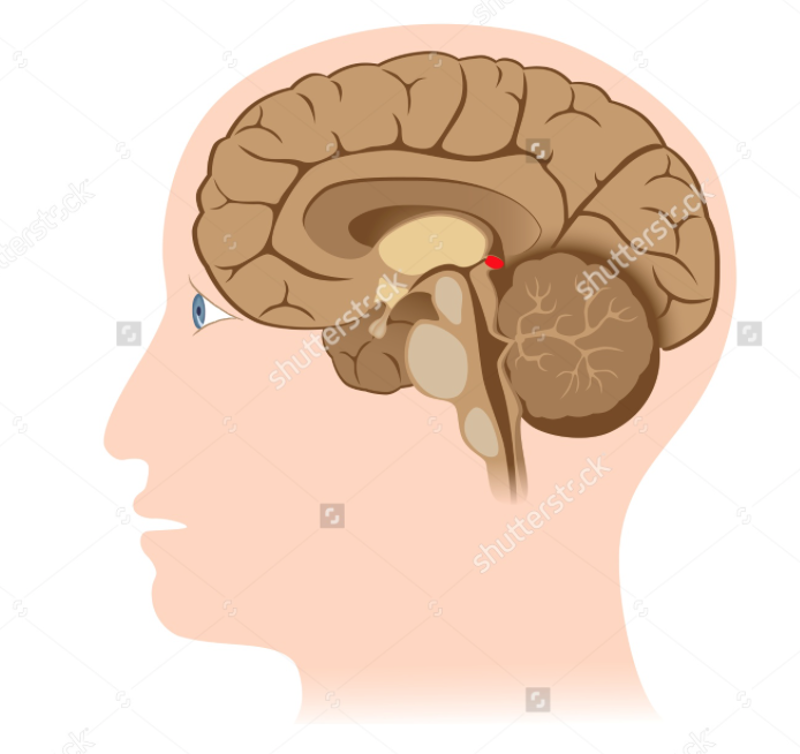

Pineal Gland